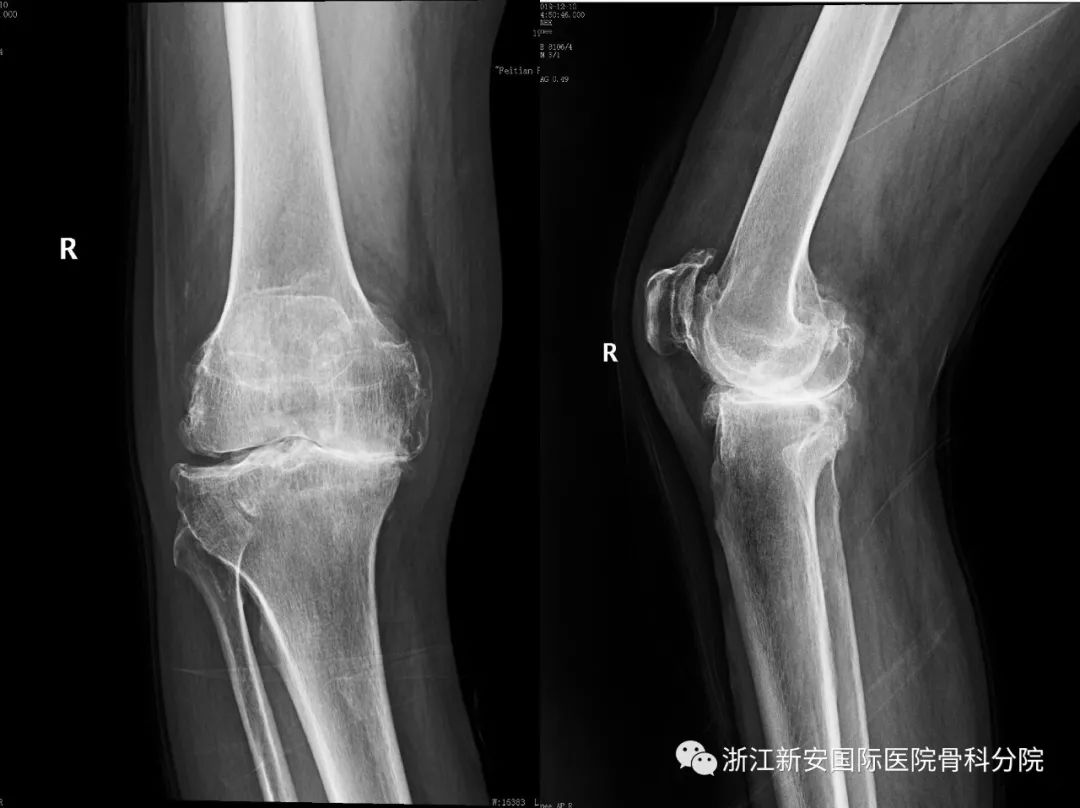

膝骨关节炎专题二严重畸形的膝关节也能让你恢复正常